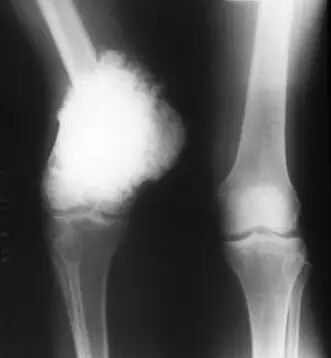

骨肉瘤是最常见的骨原发恶性肿瘤,年发病大约为2-3/100万,占人类恶性肿瘤的0.2%,占原发骨肿瘤的11.7%1-7。骨肉瘤好发于青少年,大约75%的患者发病年龄在15-25岁,中位发病年龄为20岁,小于6岁或者大于60岁发病相对罕见。

本病男性多于女性,比例约为1.4:1,这种差异在20岁前尤其明显。大约80%-90%的骨肉瘤发生在长管状骨,最常见发病部位是股骨远端和胫骨近端,其次是肱骨近端,这三个部位大约占到所有肢体骨肉瘤的85%8-11。骨肉瘤主要发生在干骺端,发生于骺端和骨干的病例相对罕见。

多数患者的首发症状常为疼痛和肿胀,前者发生要早于后者,大约90%的患者在影像学上有软组织肿块,但不是都表现为局部肿胀。